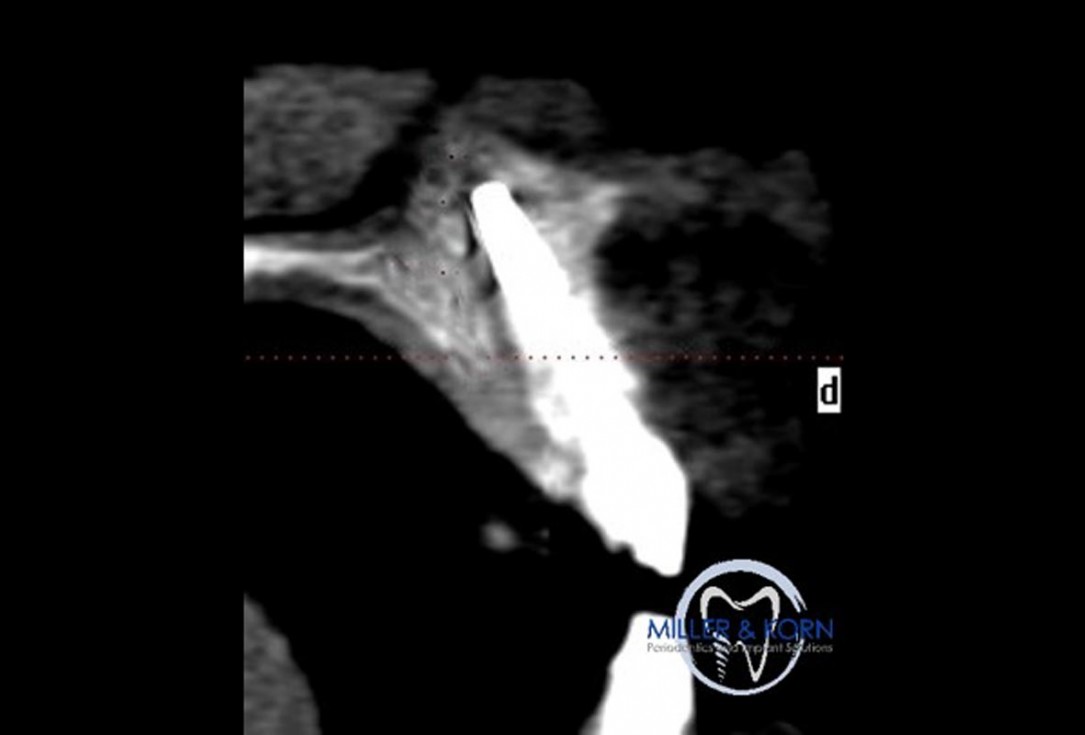

38/39 - Preoperative CT scanImmediate implant placement and correction of horizontal and vertical bone loss using an allograft bone ring, cerabone® and Jason® membrane - Drs. Miller and Korn

DVT image demonstrating horizontal and vertical amount of bone available